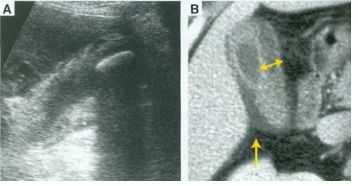

21. 40歲女性,因急性腹痛至急診處求診,理學檢查右上腹有明顯壓痛,體溫38℃,實驗室檢查AST:1070 IU/L, ALT:1810 IU/L, bilirubin (total/direct) 3.2/1.8 mg/dL,WBC:12400/μl,seg:84%,超音波及電腦斷層檢查如圖,下列敘述何者正確? (A)診斷為急性肝炎 (B)常合併肝內膽管結石 (C)Morphine是此患者止痛之首選 (D)內科治療為首選,且90%以上患者均可得到症狀改善 (E)近來之趨勢為儘早手術